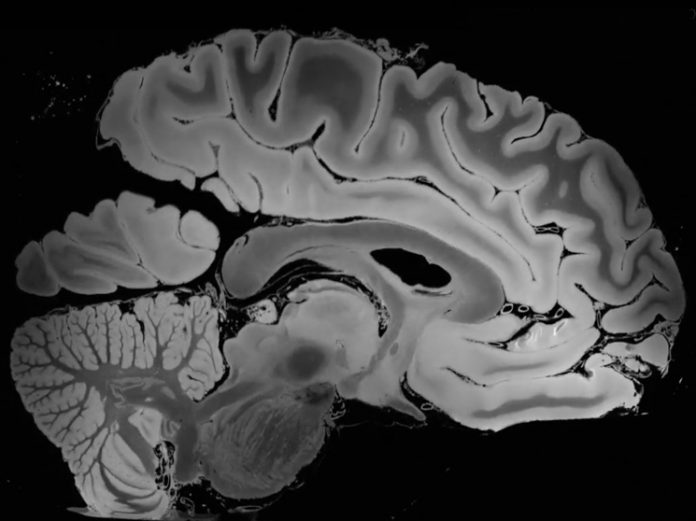

Получить трехмерное изображение человеческого мозга высокого разрешения удалось исследователям MGH в Бостоне с помощью метода магнитно-резонансной томографии. Высокое качество модели удалось получить за счет длительного пребывания мозга в сканирующем МРТ аппарате 7 Tesla.

Экспериментальное время пребывания — 100 часов. Хоть этот способ в отличии от рентгеновского безопасен для организма, однако такое длительное неподвижное время пребывания для живого человека является физически попросту неприемлемым. Поэтому для эксперимента был задействован уже неживой мозг женщины, умершей от последствий вирусной пневмонии.

Детализация, которая была получена в ходе эксперимента, позволила рассмотреть ткани мозга размером менее чем 0,1 миллиметра. В качестве магнитно-резонансного томографа был задействован 7 Tesla, который является сегодня одним из самых прогрессивным.